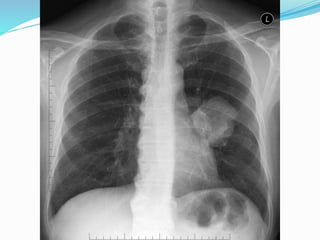

Findings on Chest X-ray

Findings on ChestX-ray  Nodule (< 3cm) vs. Mass (>= 3cm)  Location:  Peripheral (Adenocarcinoma) vs  Central (Squamous)  Single or multiple (metastases)  Atelectasis of lobe or lung  Pneumonia  Hilar and mediastinal adenopathy  Pleural effusions